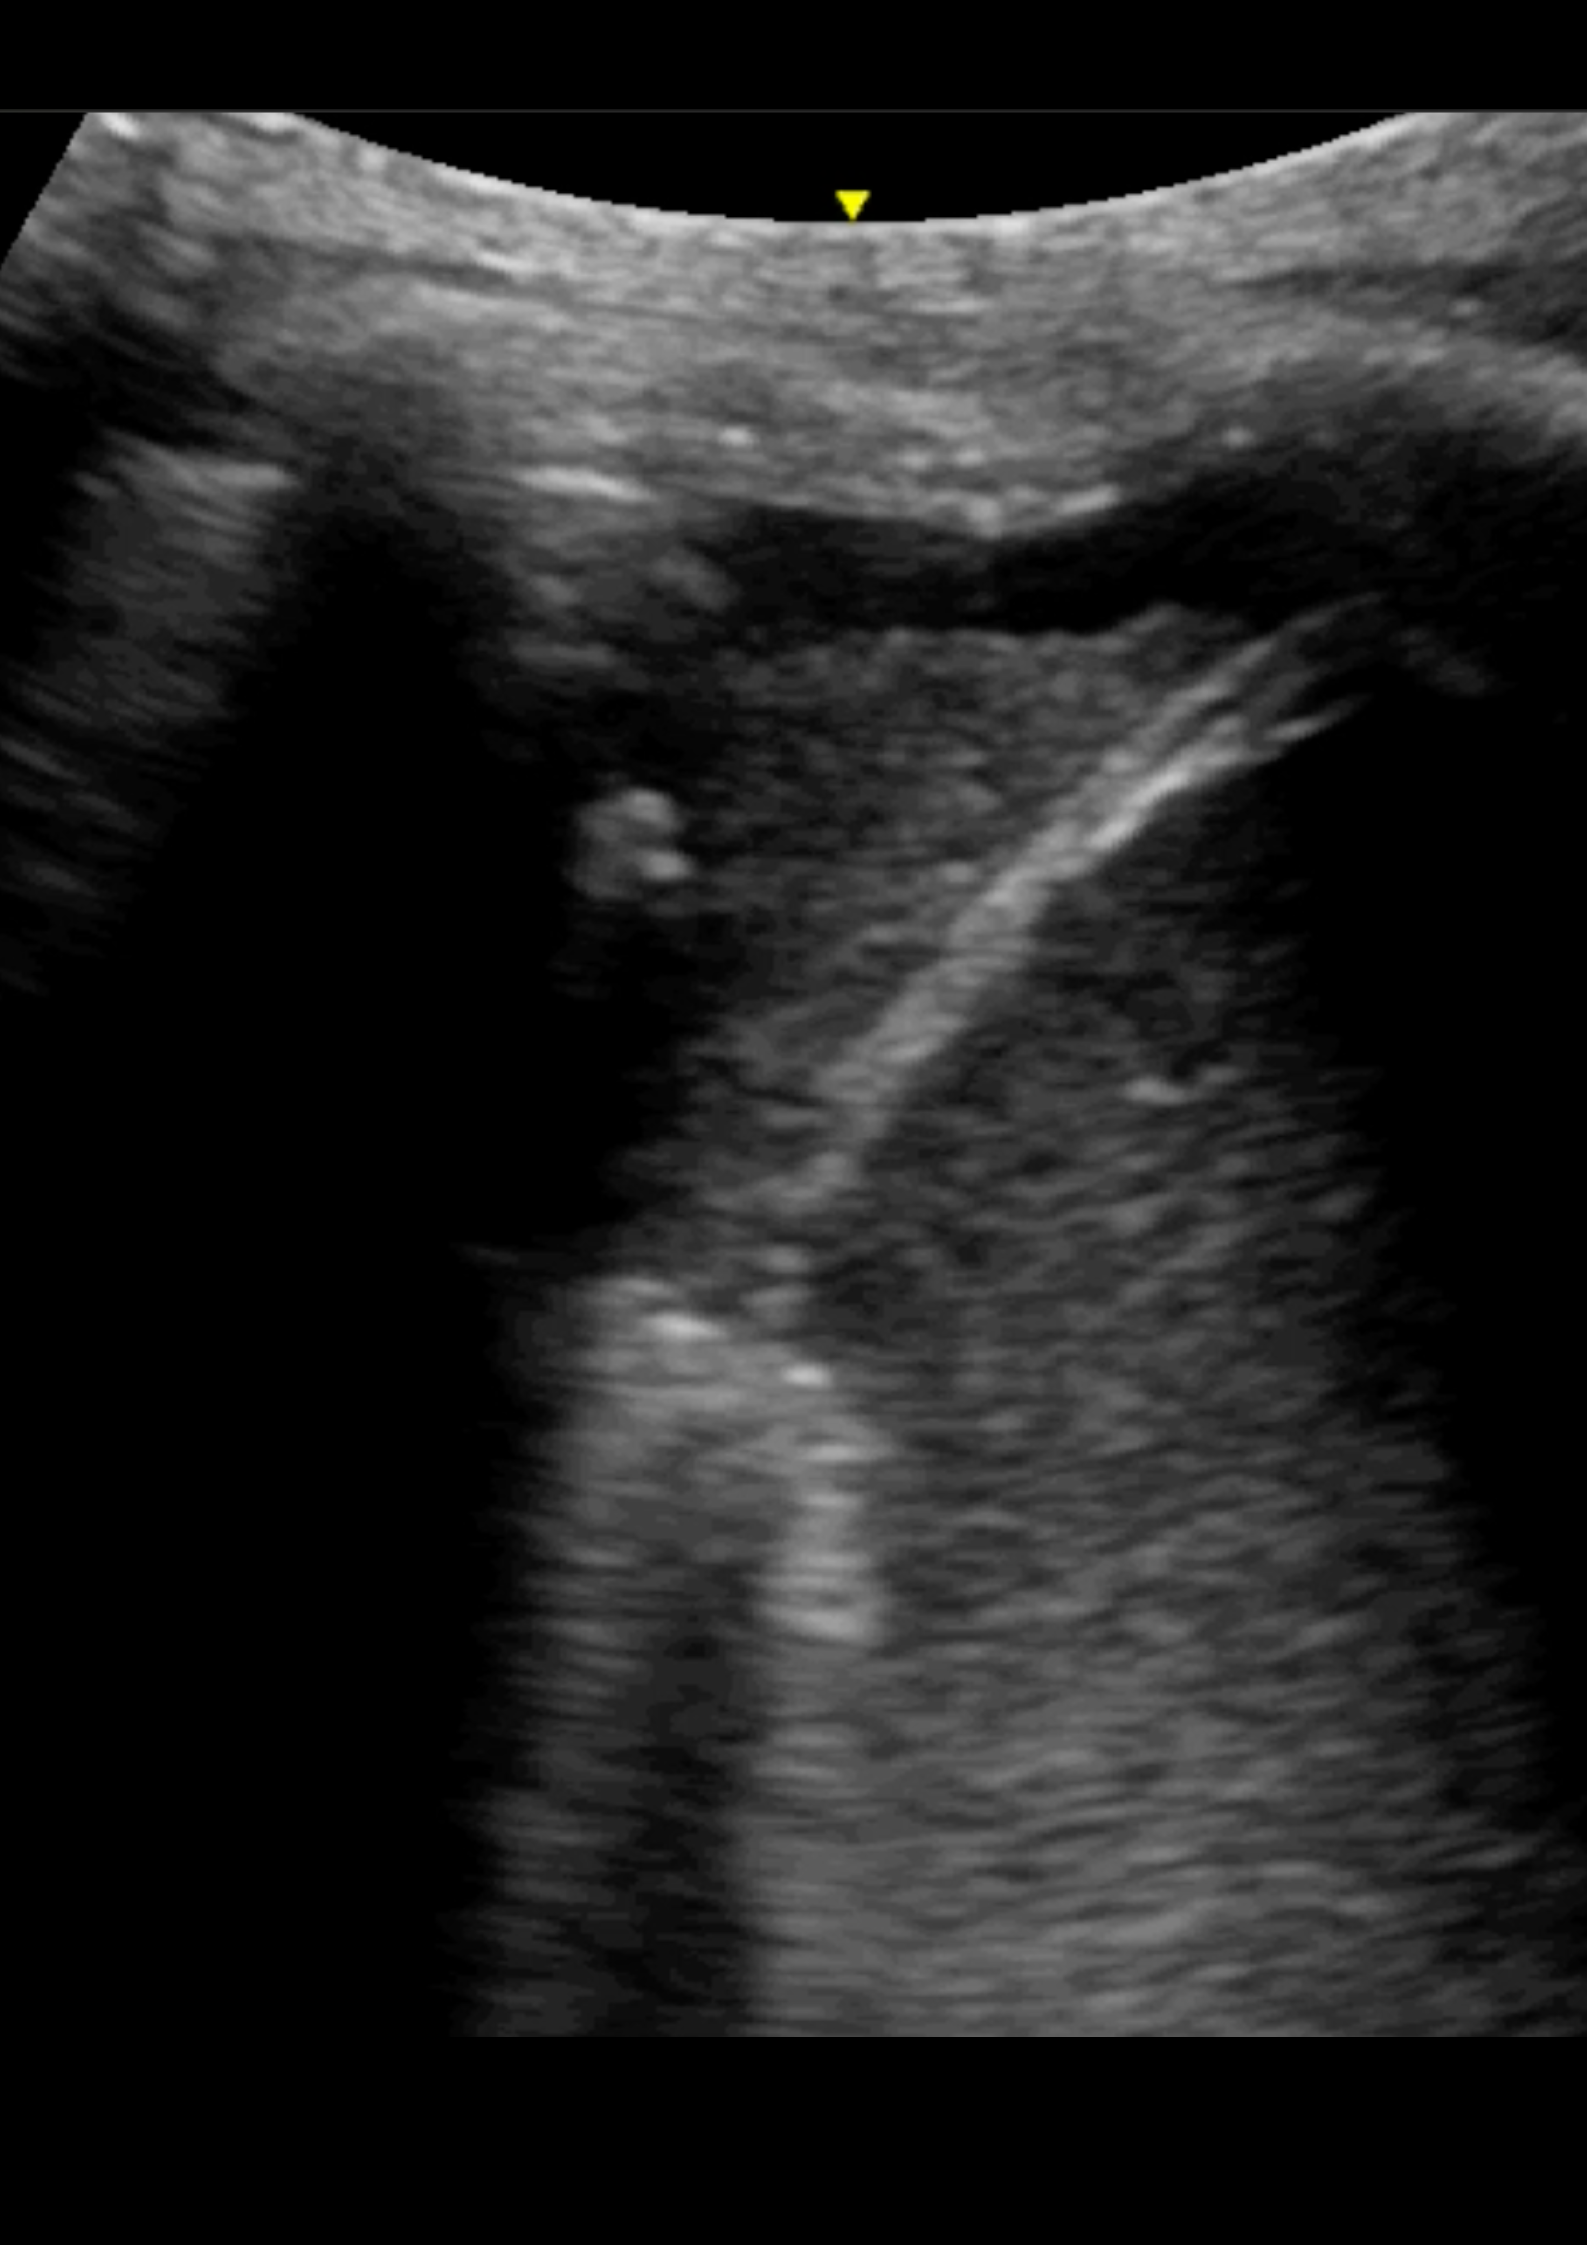

En la ecografía pulmonar observamos varios patrones de líneas B bilaterales de predominio derecho, con hallazgo de consolidación en punto PLAPS (posterolateral alveolar and/or pleural syndrome) y derrame pleural.

La ecografía pulmonar en Atención Primaria no está tan establecida como en el caso de Urgencias, sin embargo, un correcto manejo de la misma permite diferenciar entre diferentes motivos de disnea como son la descompensación cardíaca y el broncoespasmo, así como patología infecciosa. El punto PLAPS, situado en la parte postero-inferior-lateral del pulmón, es el punto más rentable para el diagnostico de las consolidaciones pulmonares así como el derrame pleural, independientemente de la posición del paciente.